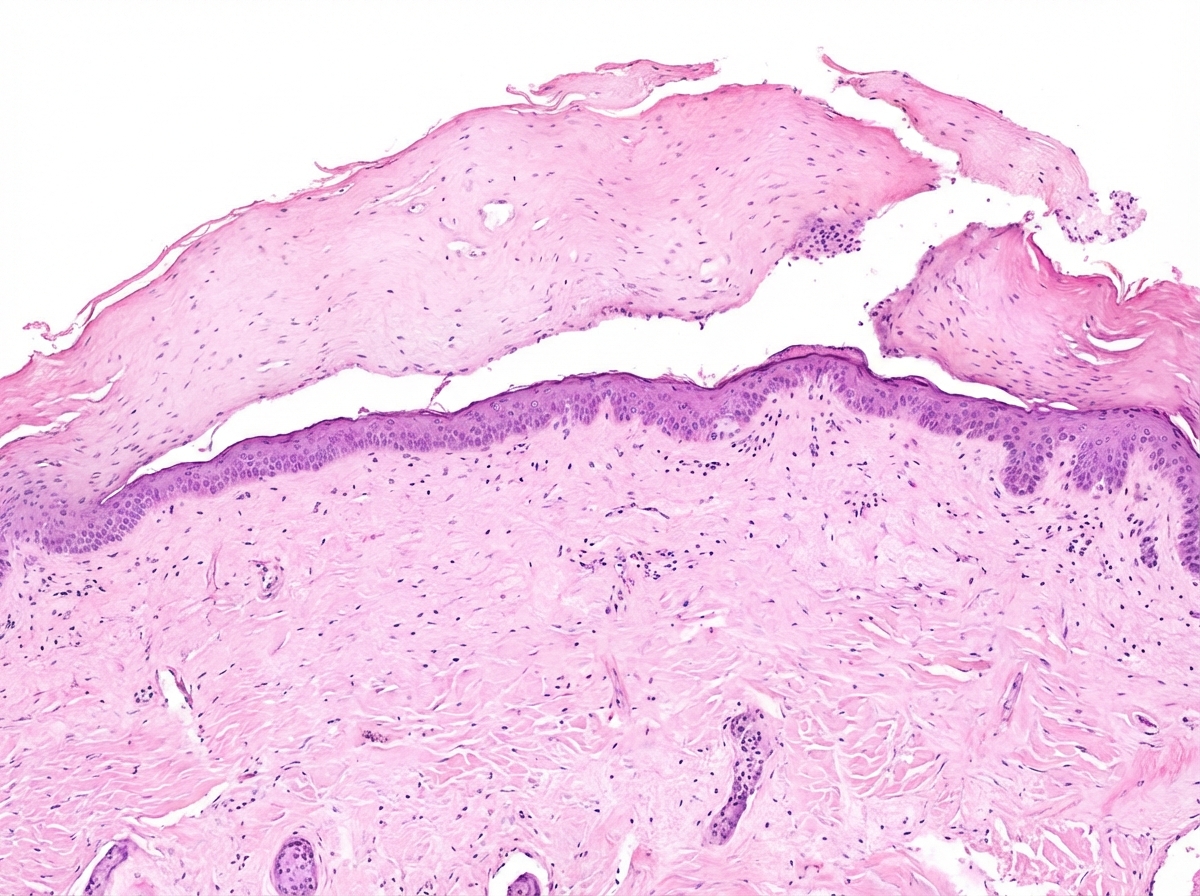

Question 11: Identify the histopathological slide shown below:

- A. Toxic epidermal necrolysis (Correct Answer)

Explanation: ***Toxic epidermal necrolysis*** - Histopathology of **Toxic Epidermal Necrolysis (TEN)** characteristically shows **full-thickness epidermal necrosis** with minimal or no dermal inflammation [1]. - This extensive epidermal death leads to the characteristic **Nikolsky's sign** and widespread skin detachment. *Lepromatous leprosy* - Histology of **lepromatous leprosy** typically reveals a large number of **acid-fast bacilli** within macrophages, forming foamy cells. - There is often a **grenz zone** (a clear zone) separating the inflammatory infiltrate from the overlying epidermis. *Pemphigus vulgaris* - **Pemphigus vulgaris** is characterized by **suprabasal acantholysis**, leading to the formation of intraepidermal blisters. - Immunofluorescence studies show a characteristic **"chicken wire" pattern** of IgG and C3 deposition on the cell surface of keratinocytes. *Mycosis fungoides* - **Mycosis fungoides** is a cutaneous T-cell lymphoma, and its histology shows an epidermotropic infiltrate of atypical lymphocytes [2]. - Characteristic findings include **Pautrier microabscesses** (collections of atypical lymphocytes in the epidermis) and cerebriform nuclei of the lymphocytes [2]. **References:** [1] Kumar V, Abbas AK, et al.. Robbins and Cotran Pathologic Basis of Disease. 9th ed. The Skin, pp. 1166-1168. [2] Cross SS. Underwood's Pathology: A Clinical Approach. 6th ed. Common Clinical Problems From Diseases Of The Urinary And Male Genital Tracts, pp. 564-565.